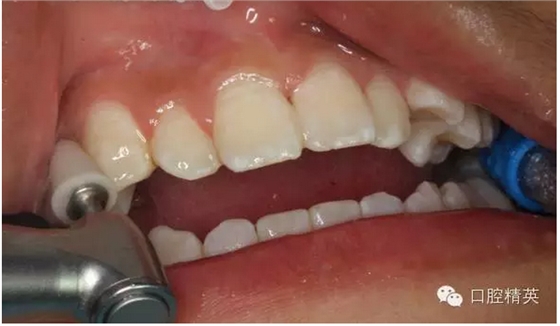

圖20.光固化樹(shù)脂+唇弓夾板固定

圖 21.修整粘結(jié)的樹(shù)脂形態(tài)

圖22.拋光樹(shù)脂